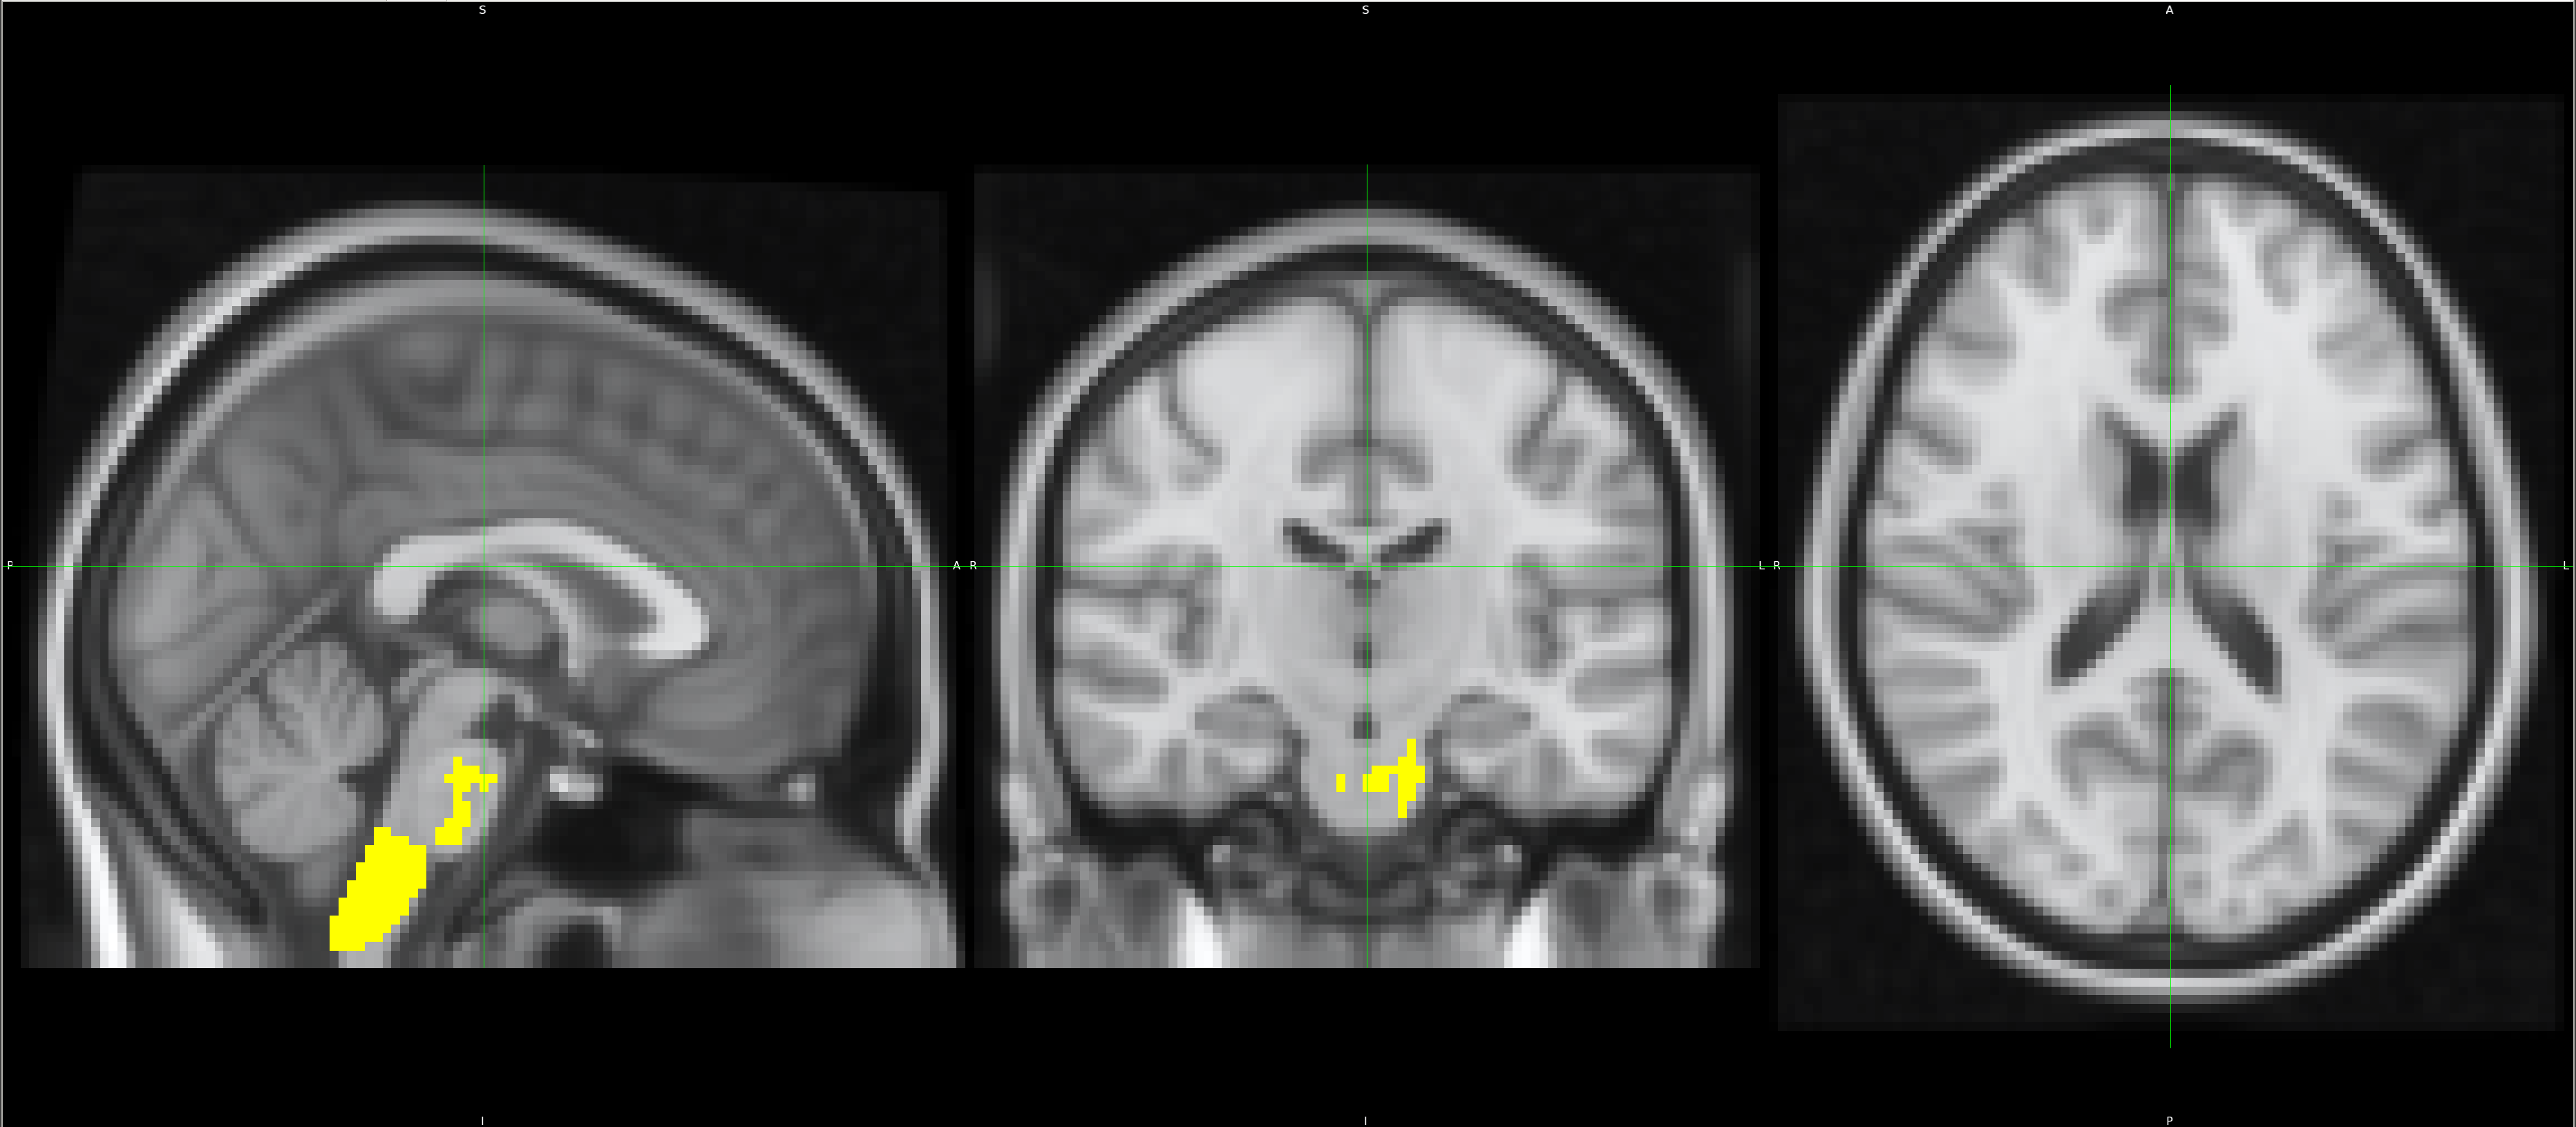

NonAth>AmFB

Showing the local differences in grey matter volume between the two groups:

Using this vertex analysis, marked differences in shape have been found in the two following areas:

[1] Left-Putamen

[2] Left-Thalamus